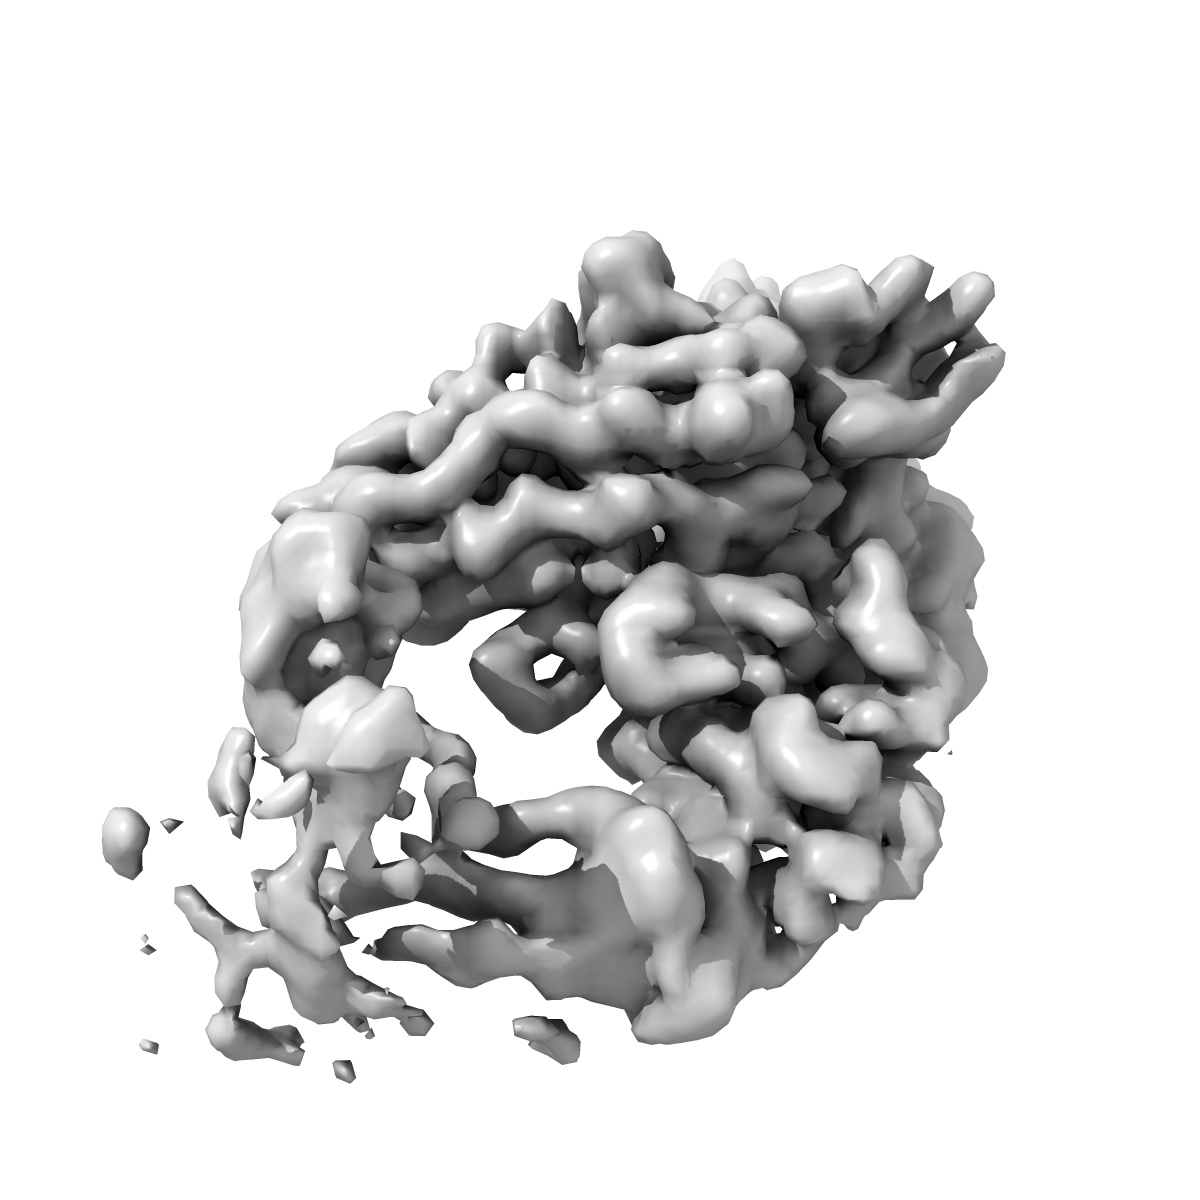

EMD-16375

SARS-CoV2 Omicron BA.1 RBD in complex with CAB-A17 antibody

Single-particle2.68 Å

Sample: SARS-CoV2 Omicron BA.1 Spike in complex with CAB-A17 antibody

Fitted models: 8c0y

Structural basis of broad SARS-CoV-2 cross-neutralization by affinity-matured public antibodies.